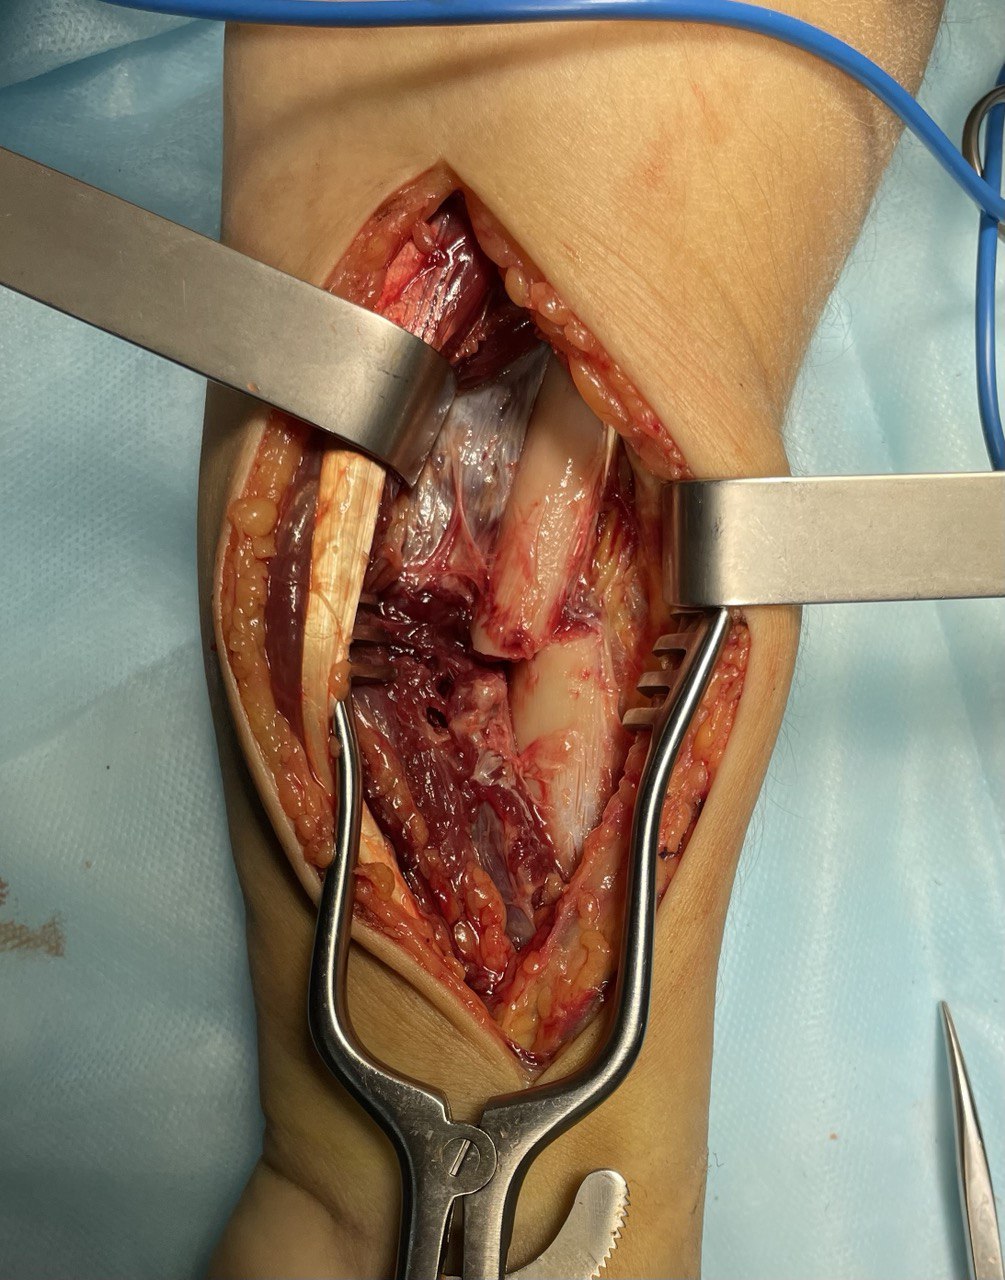

Клинический случай: внутрисуставной перелом дистального метаэпифиза лучевой кости — операция (остеосинтез пластиной)

Этап остеосинтеза: доступ, фиксация и контроль положения пластины.